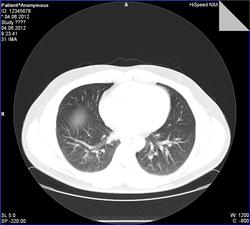

- https://radiomed.ru/sites/default/files/styles/case_slider_image/public/user/7898/0011.jpg?itok=GHLBoi7f

сделать снимок на выдохе для исключения обструкции

Обогащение рисунка, снижение пневматизации. сказать что -то конкретное -трудно. Сосудистое окно бы посмотреть. На выдохе- да было бы неплохо.

В общем-то, бросилось в глаза то, что расширены вены, преимущественно, нижних долей. При этом правые и левые венозные коллекторы без явного расширения и аномалий, предсердие с ушком без проблем при нативной КТ. Так же заметил "нежные" ретикулярные изменения в переднем сегменте верхней доли справа.

Ой, прошу прощения! Я тормоз! Там же 3 серии: 1 - топограмма, вторая на вдохе, а третья - на выдохе)))) Сергей Николаевич, Ваши иллюстрации с серии на выдохе.Радостно посмотрела на вдохе - чисто!

Пример скана на одном уровне при фазах дыхания).

По экспираторной КТ - норма, "ловушек" нет, значит и обструкции нет, что и требовалось доказать, что соответствует заключению по ФВД ( сам интерпретировать параметры не смогу полноценно, со времен учебы подзабыл, а во время работы вникать в цифры не приходилось). Может, кто разбирается и прокомментирует.

Наверняка и у Вас есть функция просмотра всех серий, просто её надо найти). Пробежала ту статью, у нашего пациента ничего подобного в фазу выдоха нет... фуууу, норма всё-таки))))

Предоставленные в первом посте томограммы - экспираторная КТ, можно не только на слово

Томография: рентгенологически патологии не визуализировано